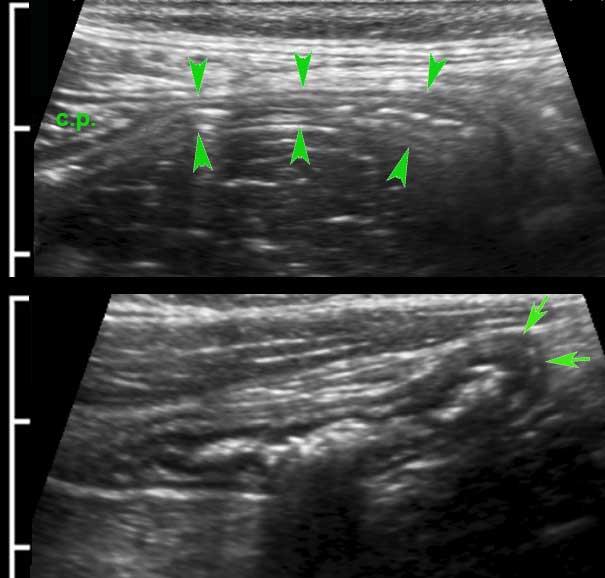

Lớp mỏng này (đầu mũi tên) tăng âm trên siêu âm và có thể thấy ở ruột non của bệnh nhân gầy.

Mặc dù không có ý nghĩa lâm sàng, việc nhận diện riêng biệt đám rối Auerbach trên siêu âm cho thấy độ phân giải cao của siêu âm so với CT và MRI.

Lớp cơ của đại tràng khác với lớp cơ của ruột non.

Lớp cơ dọc chỉ giới hạn ở ba dải định hướng dọc, được gọi là dải cơ dọc kết tràng (teniae coli). Trong đại tràng rỗng, xẹp ở những bệnh nhân gầy, ba dải cơ dọc này (đầu mũi tên) thường có thể được xác định bằng siêu âm như một vùng dày lên cục bộ của lớp cơ, tách biệt với lớp cơ vòng bởi một đường tăng âm mỏng.

Trong hình ảnh theo chiều dọc này, chỉ xác định được một dải cơ dọc (đầu mũi tên).